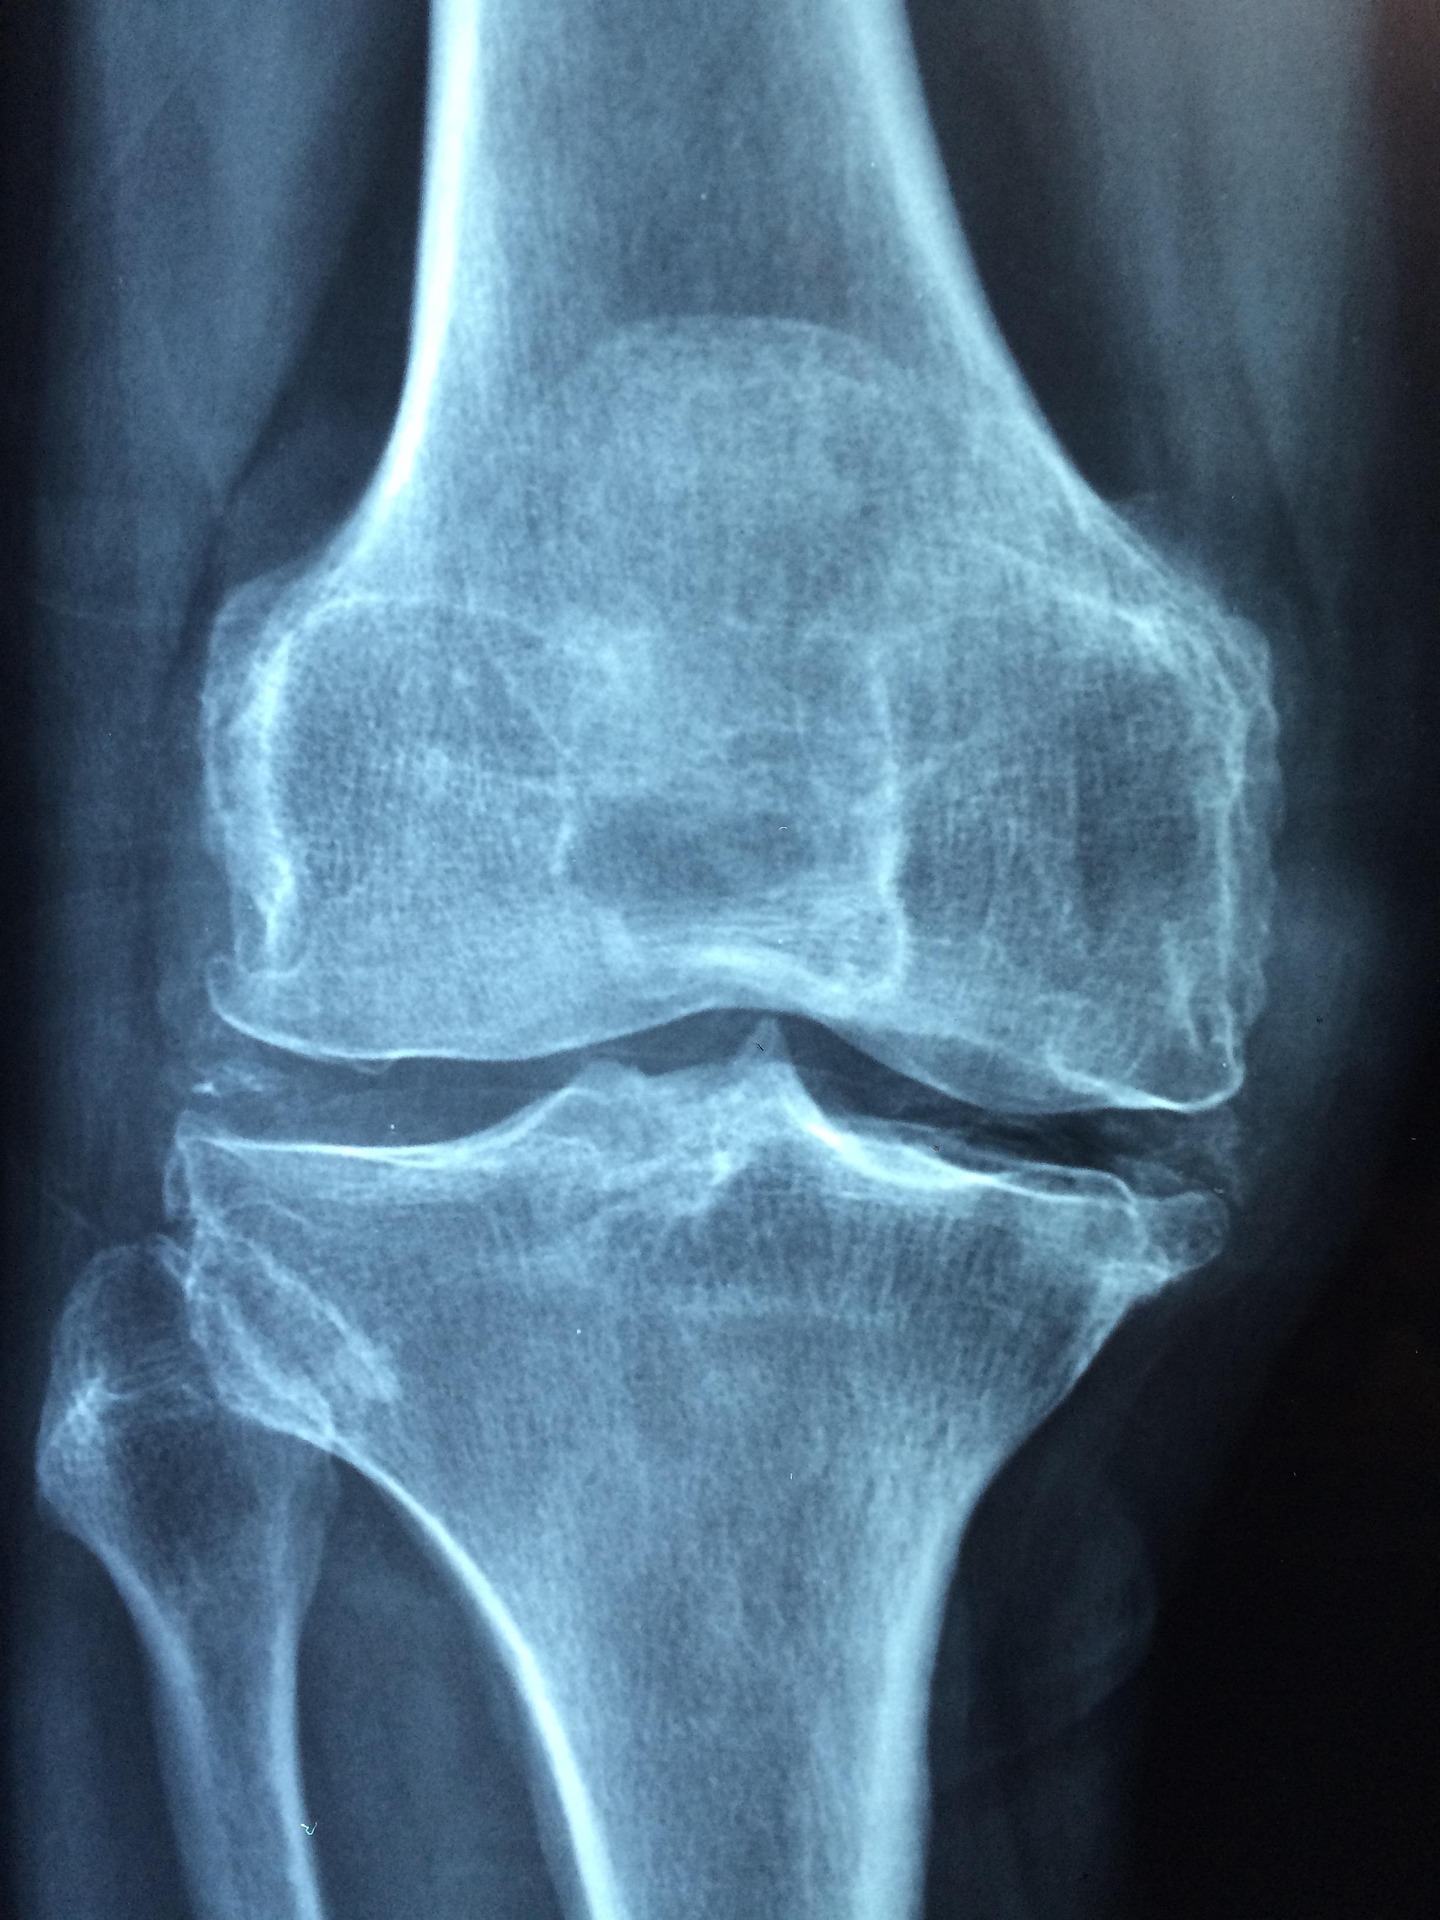

무릎 연골주사는 주로 히알루론산 성분을 사용해 관절 내 윤활액을 보충하는 치료법입니다. 관절염으로 인해 마찰이 심해진 무릎 관절에 주사를 놓아 통증을 줄이고 움직임을 부드럽게 만듭니다. 대표적인 주사로는 콘쥬란, 히알루론산 주사, 시노비안 등이 있습니다. 이 주사는 윤활제 역할을 하며, 관절의 마찰을 줄여 통증을 완화하는 데 도움을 줍니다.

이 치료는 특히 퇴행성 관절염 초기나 중기 단계에서 효과적이며, 의료 전문가의 진단 후 시행됩니다. 단, 연골 손상이 심각한 말기 관절염(4단계)에서는 효과가 제한적일 수 있습니다.

무릎 연골주사는 관절 내 마찰을 줄여 통증을 완화하고, 무릎의 움직임을 부드럽게 만드는 데 주로 효과적입니다. 많은 환자들이 주사 후 통증이 줄어들고 일상생활에서 무릎 움직임이 편해졌다고 보고합니다. 특히 퇴행성 관절염 초기 단계에서 더 좋은 결과를 보이는 경우가 많습니다.

다만, 연골주사는 연골을 재생시키는 치료법은 아닙니다. 연골 손상을 복구하기보다는 통증을 줄이고 관절 기능을 개선하는 데 초점이 맞춰져 있습니다. 따라서 치료 효과는 개인의 관절 상태와 주사 횟수에 따라 다를 수 있습니다. 보통 1~3회 주사를 일정 간격으로 맞는 경우가 일반적이며, 효과는 몇 주에서 몇 달까지 지속될 수 있습니다.